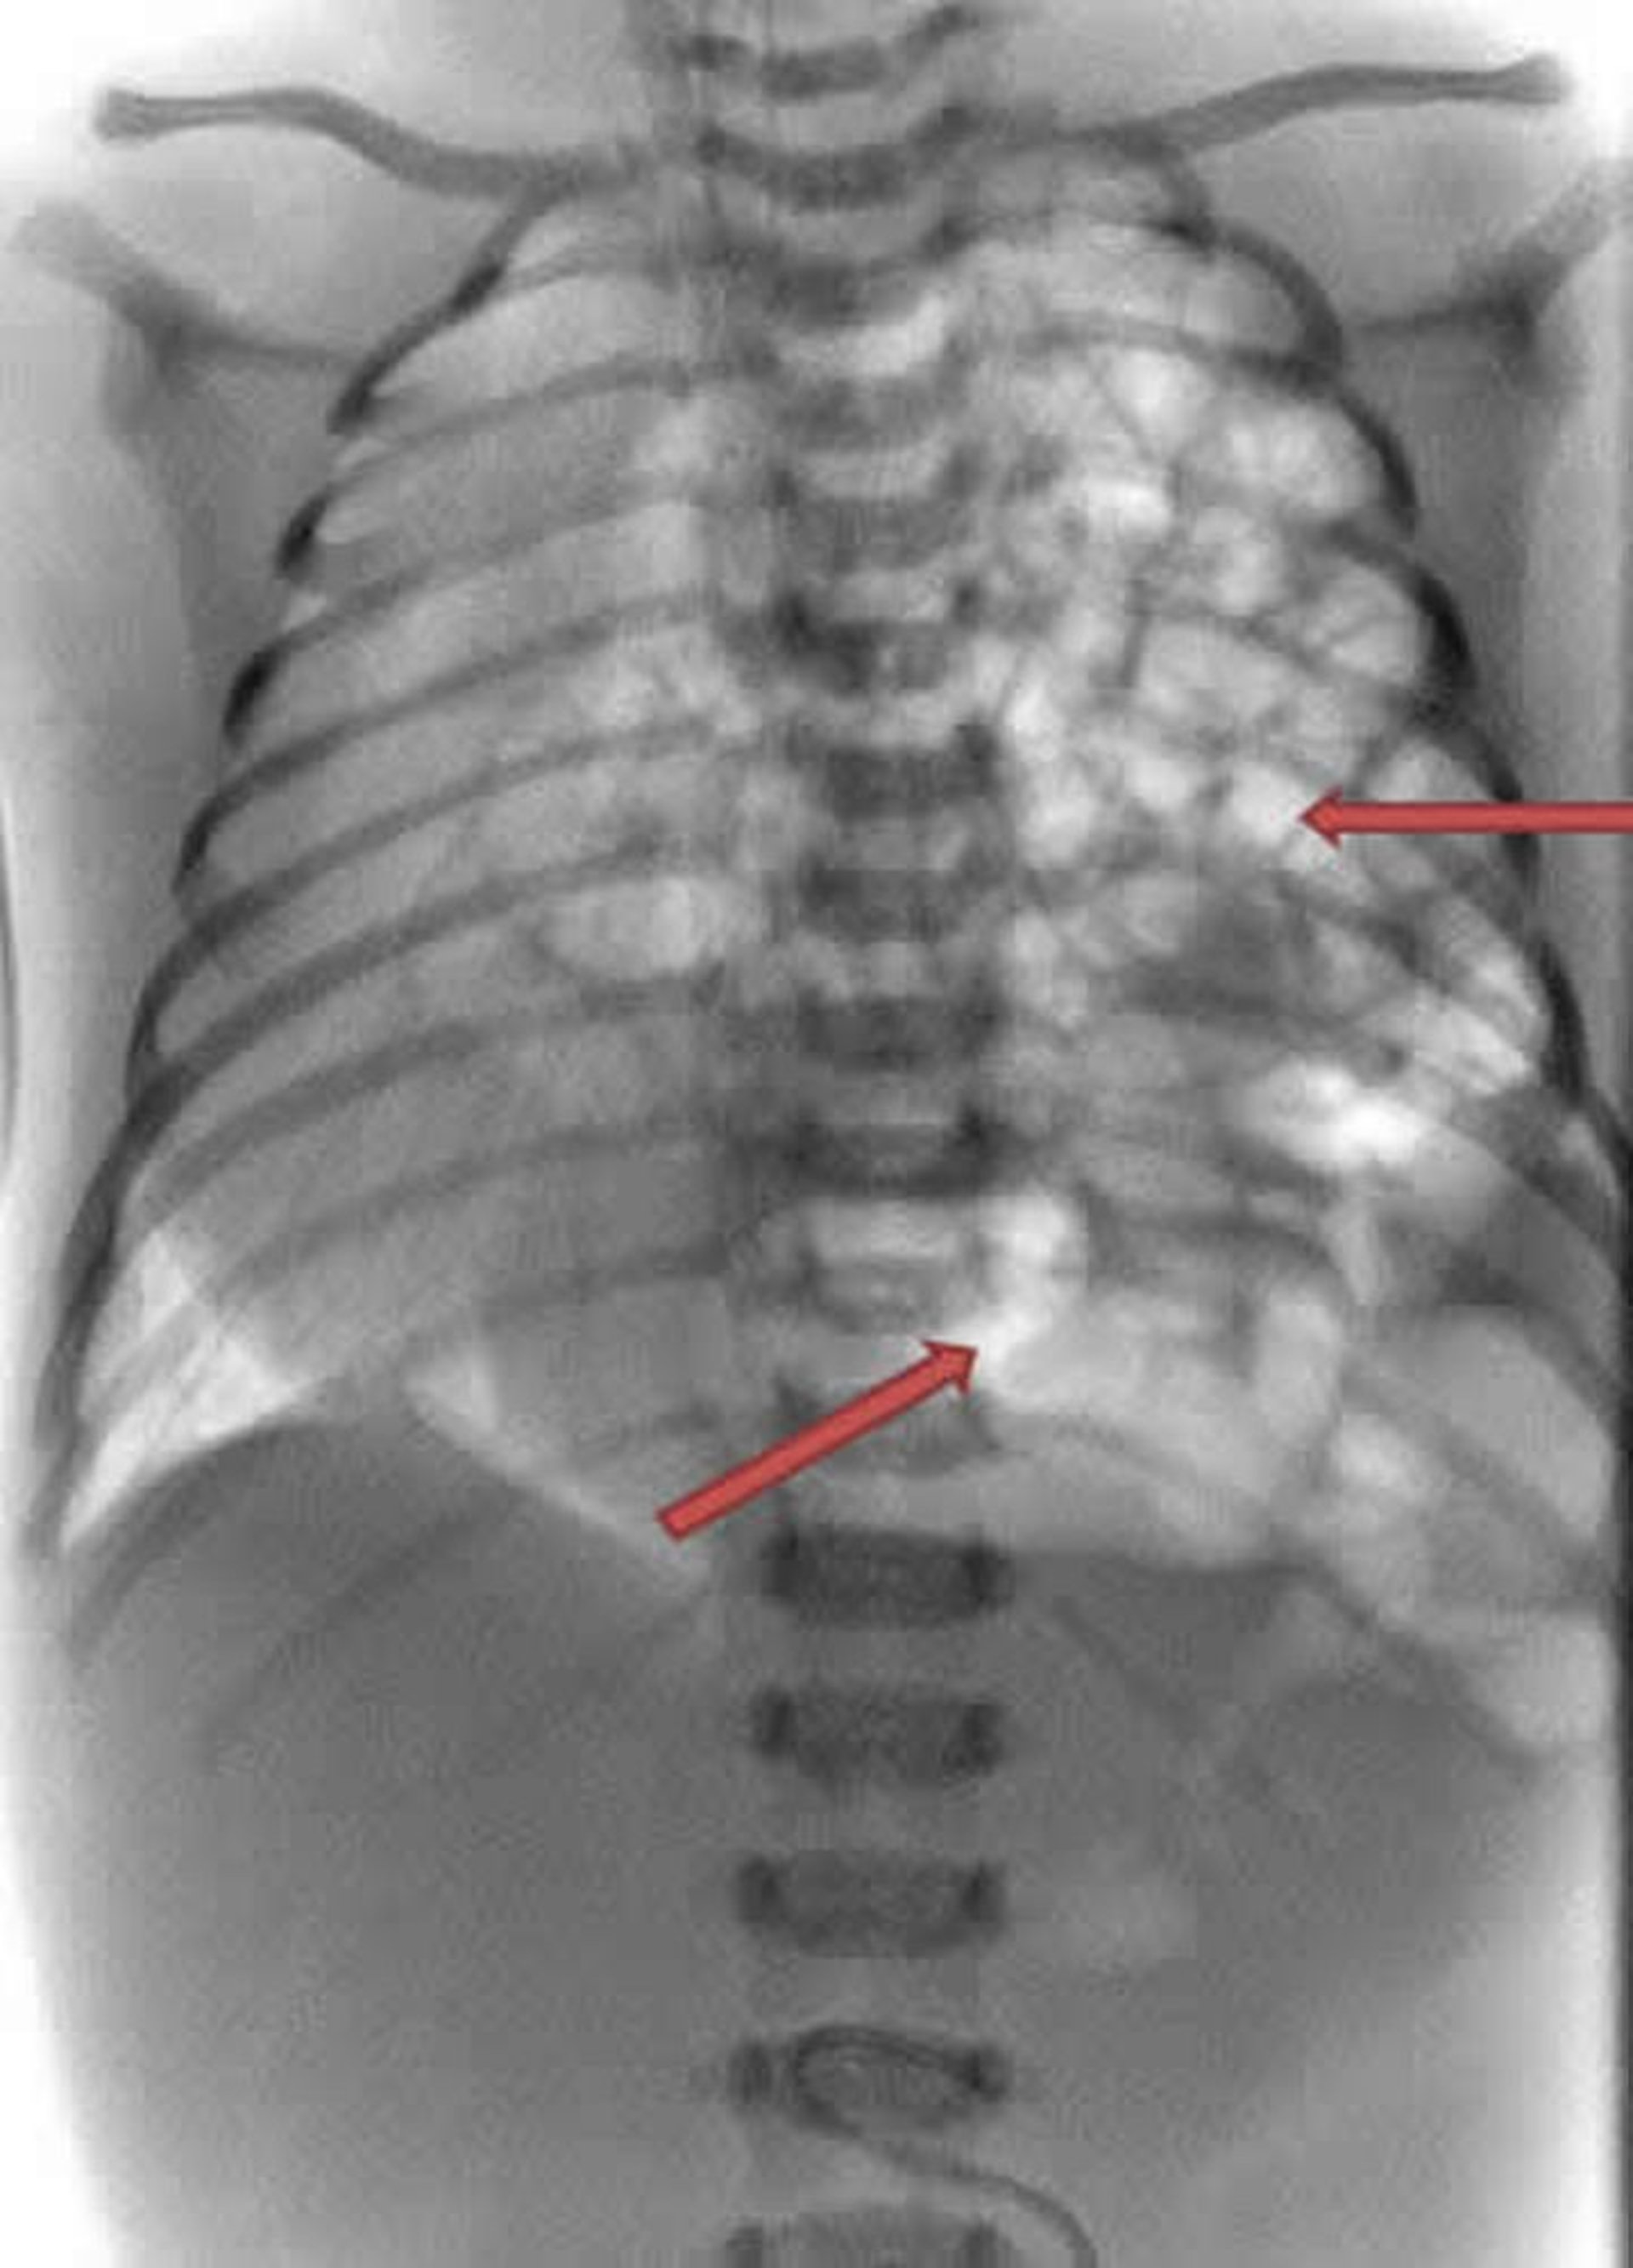

Diaphragmatic Hernia

This x-ray of a newborn shows the intestines (white coils) are protruding into the left side of the chest (arrows).